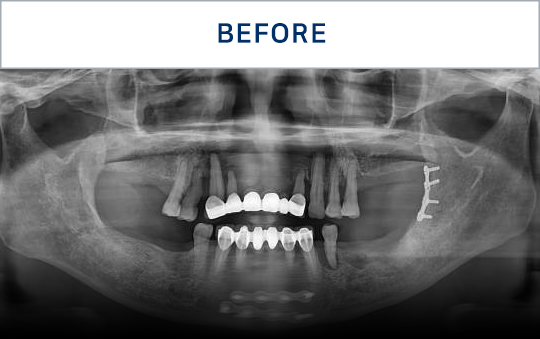

准确掌握口腔状况

了解所需的治疗方向

通过CT, 扫描等数字设

备拍摄后,

进行精密分析

考虑骨骼状态与神经位置,

制定种植位置与手术计划